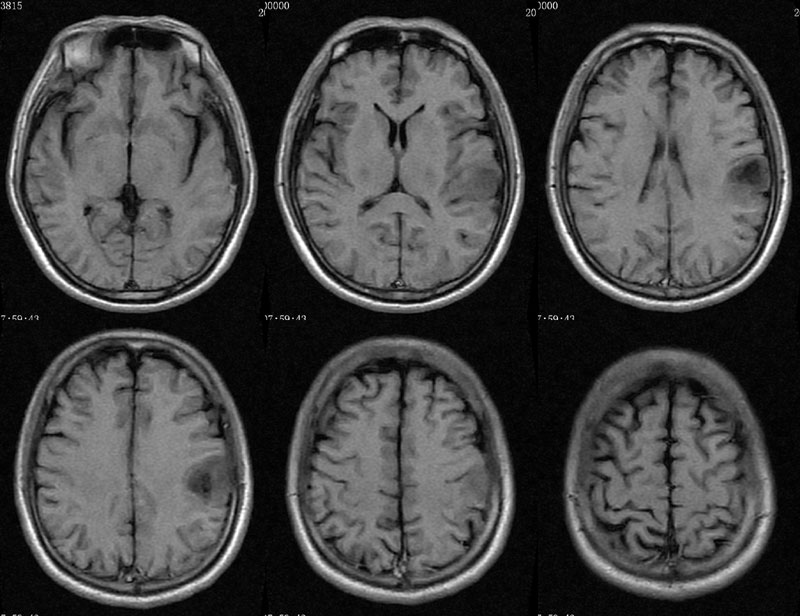

男性,46岁。

主诉:头晕、头痛2月余,加重10天。

现病史:患者2月余前出现头晕,呈天旋地转,阵发性,伴头痛,多于下午发作,伴右侧口角麻木。近10天患者自觉头晕头痛症状加重。

术后病理多形性胶质母细胞瘤 WHO Ⅳ级。

免疫组化:Vimentin(+),GFAP (+),MGMT个别(+),P53约10%(+),Ki67约20%。

左侧顶叶斑片状异常信号,T1低信号,T2高信号,增强后不均匀强化。左侧顶叶多形性胶质母细胞瘤,学习了。